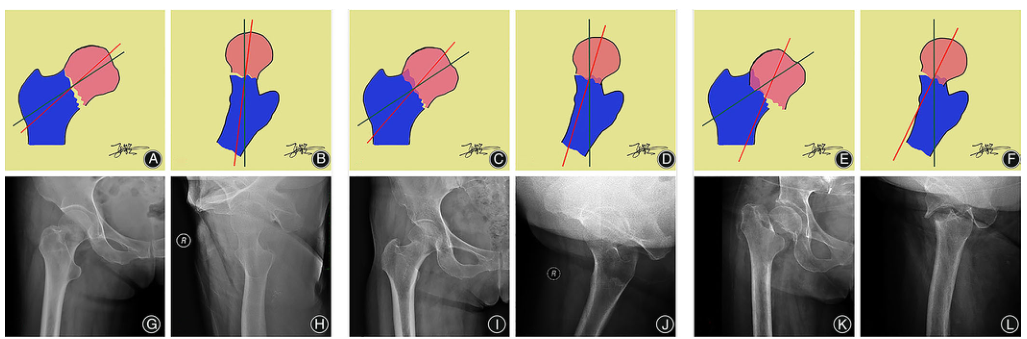

CDAC分型方法 根据股骨头在正位和轴位的联合偏移角度,建立了CDAC分型, 如图1-2所示。 CDAC主要包括三种类型:联合偏移角度内收型(ADT)、联合偏移角度外展型(ABT)和联合偏移角度特殊型(SPT)。对于联合偏移角度内收型(ADT)型,股骨头在骨盆正位向内收方向移位,在髋关节轴位向后移位(图2.AB),且具有三个亚型: I型(联合偏移角度≤35?,图3.ABJH)、II型(35?<联合偏移角度≤60?,图3.CDIJ)和III型(联合偏移角度>60?图3.EFKL)。对于联合偏移角度外展型(ABT),股骨头在骨盆正位时向外展方向移位,在髋关节轴位时向后移位(图2.CD),也具有三个亚型,I型(联合偏移角度≤20?,图4.ABJH)、II型(20?lt;联合偏移角度≤35?,图4.CDIJ)和III型(联合偏移角度>35?,图4.EFKL)。对于联合偏移角度特殊型(SPT),股骨头在骨盆正位向内收方向移位,在髋轴位向前移位(图2.EF)。这种类型是极其罕见的,由于这种类型意味着股骨头出现了较大的旋转移位,因此会有极高的并发症发生率(图5)。

图三